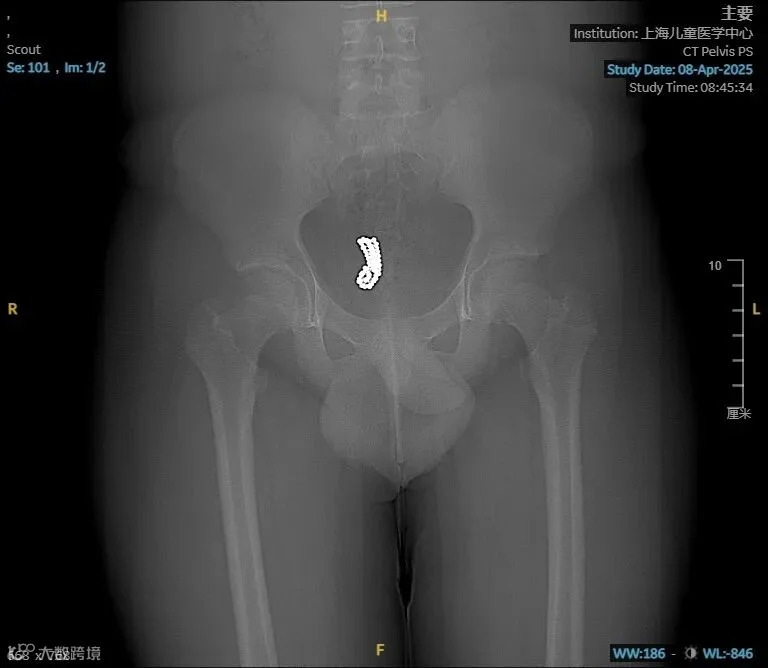

这名少年患者因青春期好奇心驱使,自行将52颗直径约5毫米的珠子经尿道塞入膀胱。4天后,出现了排尿困难、下腹疼痛等症状,在家人的陪同下前往医院就诊。

CT影像显示,这些珠子全部沉淀在膀胱最下端,不仅造成尿路梗阻,更可能因持续压迫导致膀胱黏膜损伤。